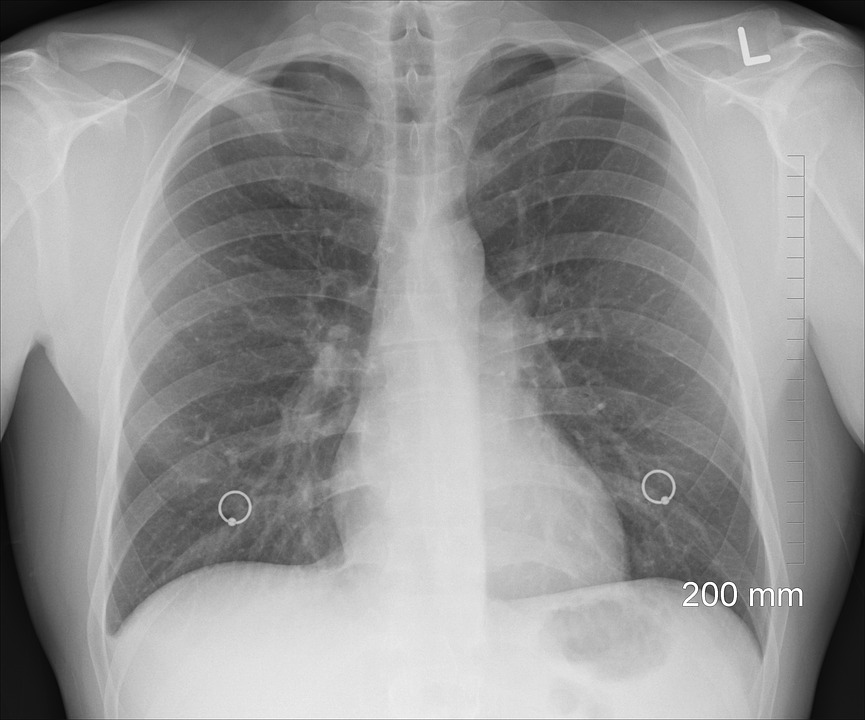

At this point, it’s no secret that being placed on the organ transplant list is no guarantee of survival if patients are in need of a new heart, or liver, or lung. One of the ways that this problem can be solved is by reconstructing damaged organs so that they don’t need to be replaced, to begin with. In a new breakthrough, scientists have found a new way of bioengineering lungs, which could save thousands of lives.

The breakthrough is courtesy of researchers from the School of Engineering and Applied Science at Columbia University, Futurism reports. They were able to preserve the vascular network of a lung that they were creating a scaffold for. In addition, the researchers were able to do this by also getting rid of the damaged epithelial lining and then replaced it with healthy cells.

As achievements go, this is a huge win for the medical community as it can substantially change how lung diseases can be treated in the future. What’s more, it could dramatically reduce the number of people who die from respiratory diseases, including lung cancer.

"We reasoned that an ideal lung scaffold would need to have perfusable and healthy vasculature, and so we developed a method that maintains fully functional lung vasculature while we remove defective epithelial lining of the airways and replace it with healthy therapeutic cells. This ability to selectively treat the pulmonary epithelium is important, as most lung conditions are diseases of the epithelium," Vunjak-Novakovic said.

What makes this breakthrough really special is how it will have an immediate impact on the survival rates of those that require a lung transplant. With just 20 percent of donor's lungs actually being viable for transplants, there is currently a severe shortage that this new method can cure.